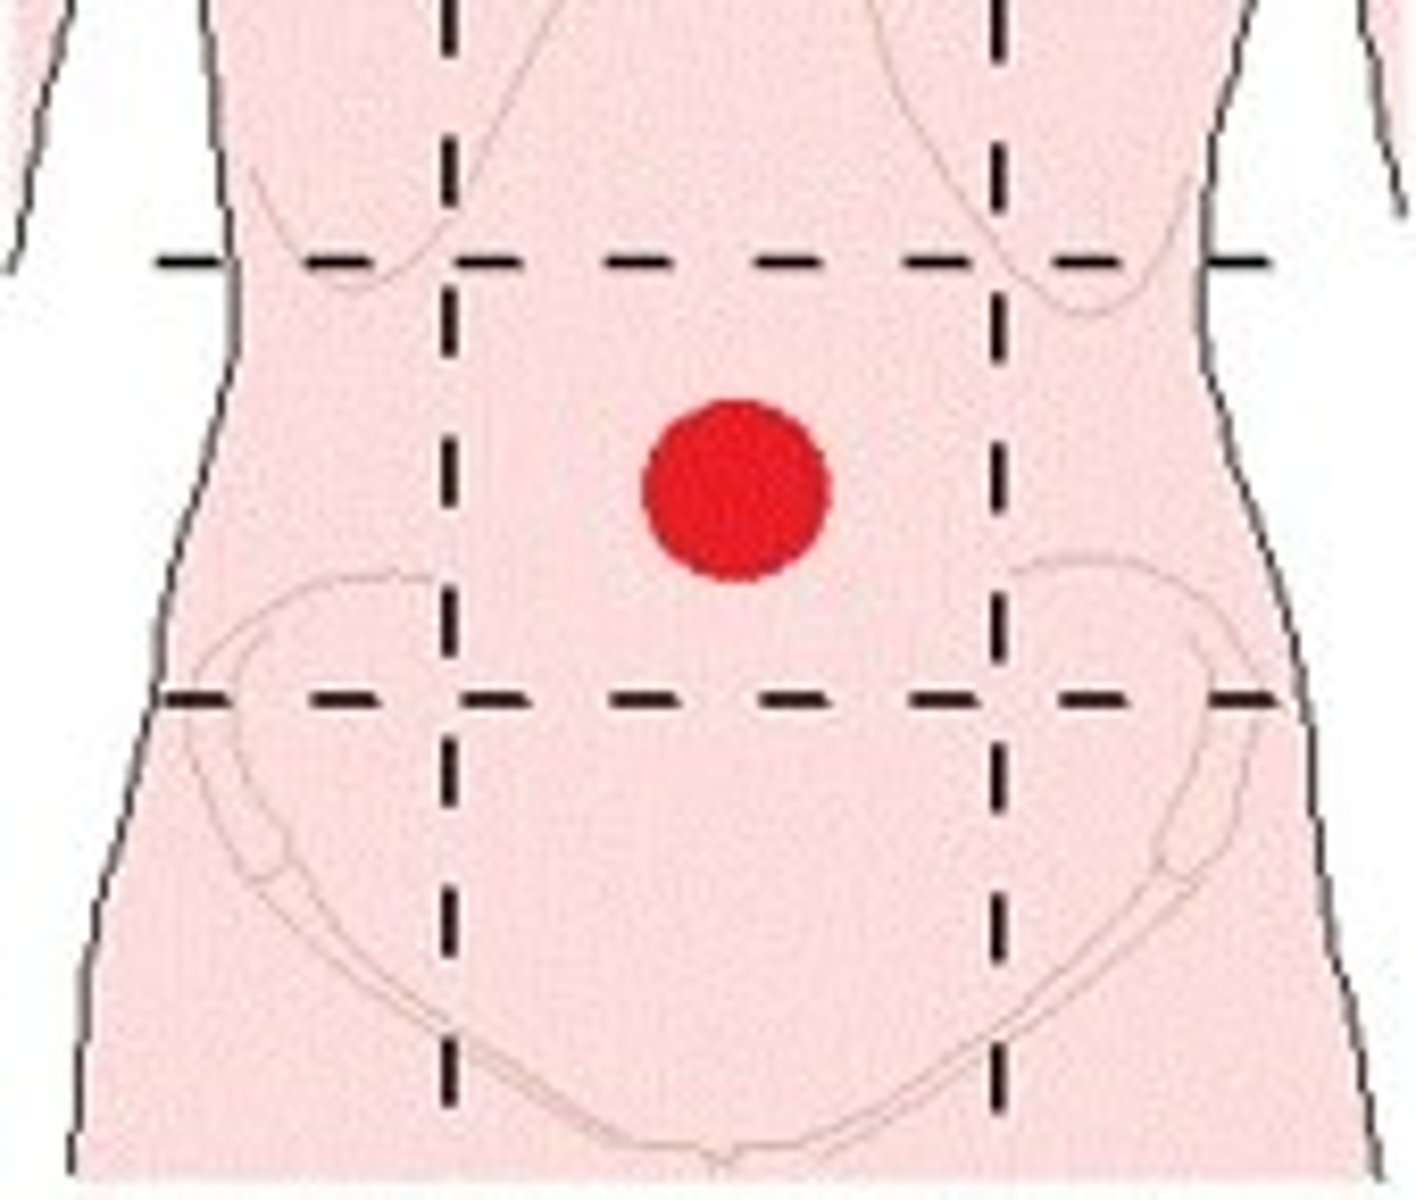

Umbilical

Belly Button